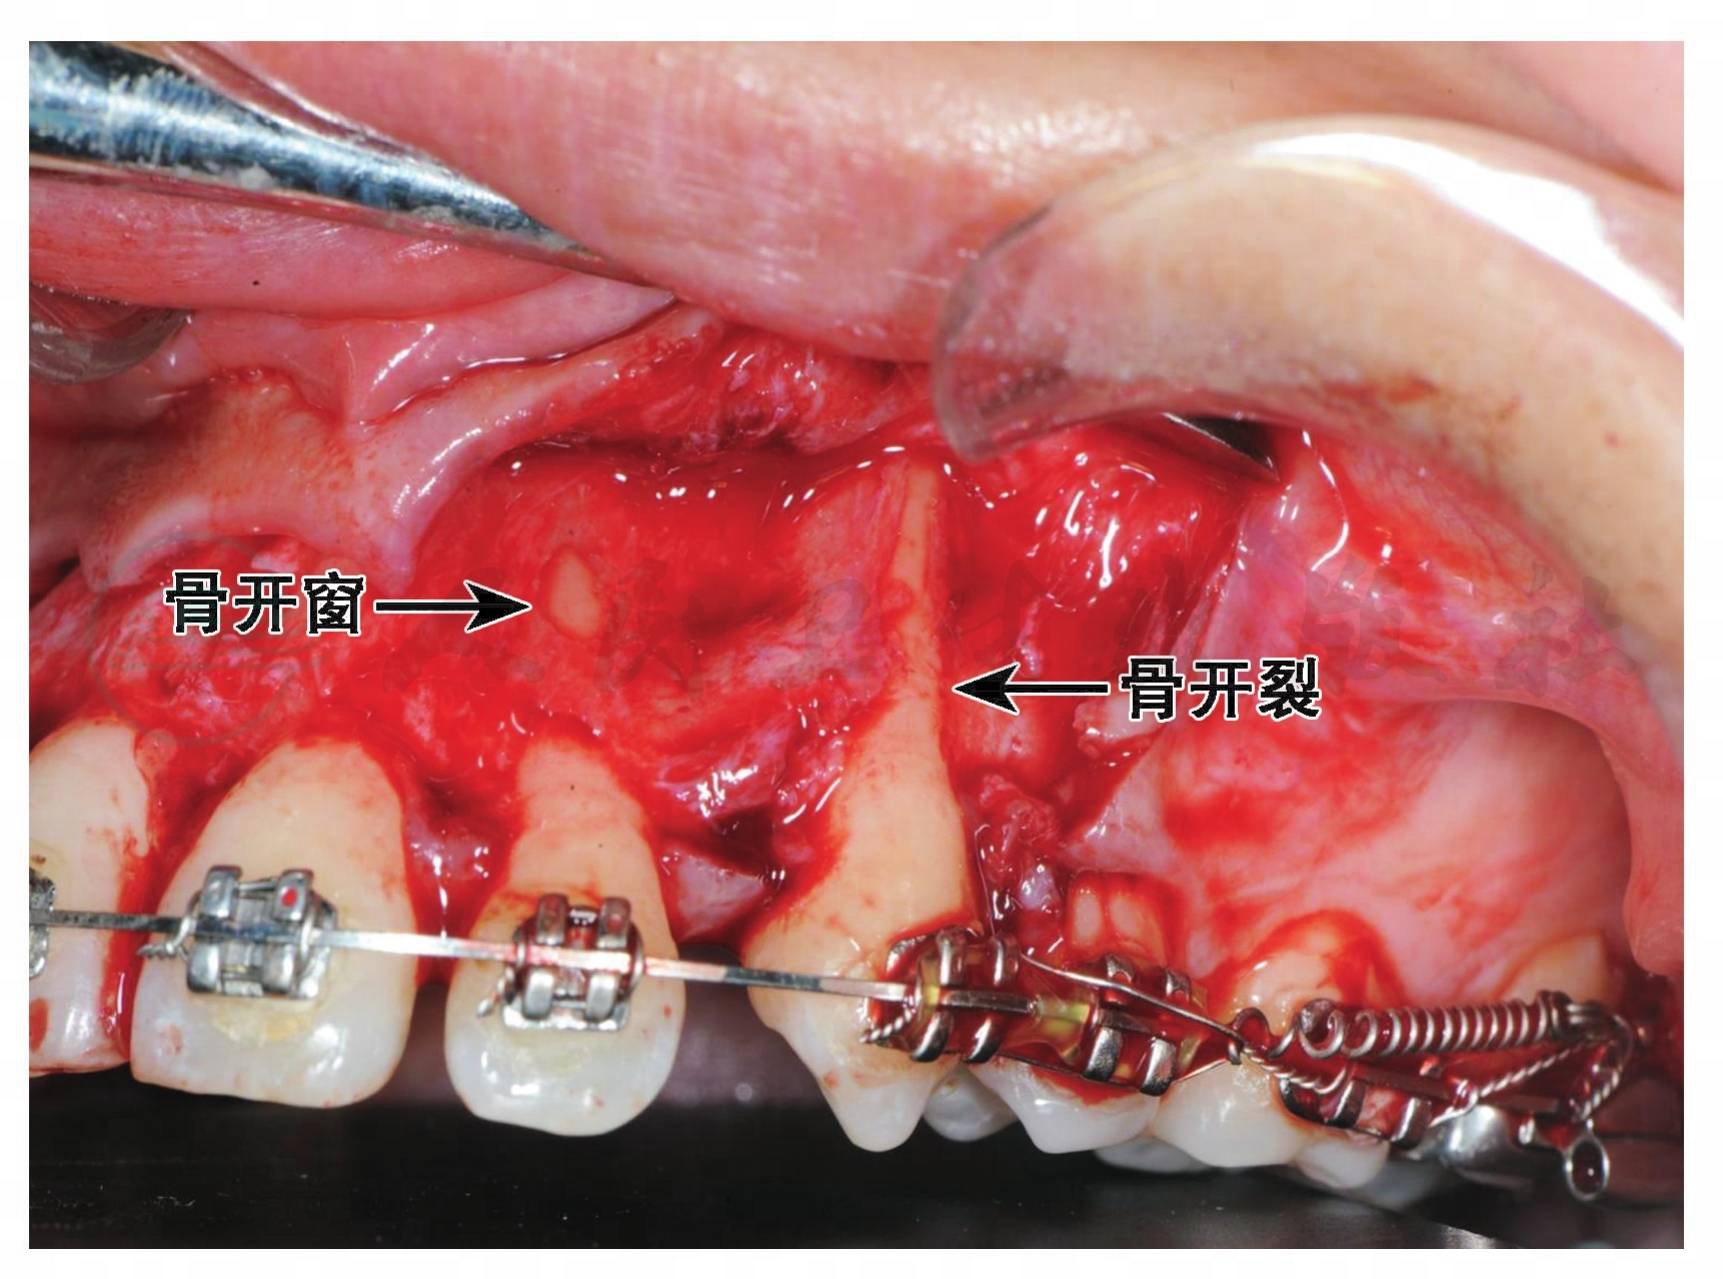

在上、下颌的前牙区、下前磨牙区及上颌第一磨牙区,由于唇颊侧骨板很薄,牙的颊向错位、牙隆凸过大或骨质吸收等,可能发生牙槽嵴畸形,根面的骨质很薄甚至缺失,根面仅覆盖骨膜和增厚的牙龈,容易发生牙龈退缩或深牙周袋。若骨剥裸区延伸至牙槽嵴边缘,即出现V形的骨质缺损,称为骨开裂(dehiscence),易引起牙龈呈V形退缩;有时骨嵴顶尚完整,而根面牙槽骨缺损形成一圆形或椭圆形的小裂孔即为骨开窗(fenestration)(图1)。牙槽嵴畸形能使膜龈手术的情况复杂化。

图1骨开窗和骨开裂

(北京大学口腔医学院徐筱医师提供)